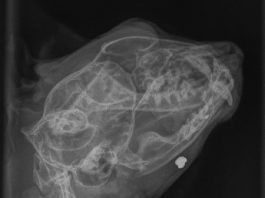

Who shot Cat the cat?

This x-ray belongs to a cat called Cat. Seriously, that’s his name – no typo. It’s the best his owner could come up with...